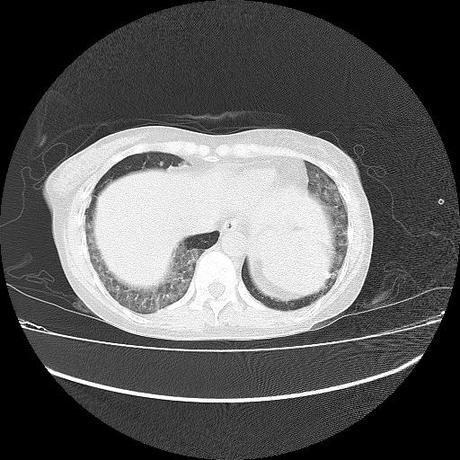

El parénquima pulmonar con areas parcheadas difusas en vidrio despulido combinadas con otras areas hipodensas de baja atenuación debidas a atrapamiento aéreo y engrosamiento intersticial y zonas de fibrosis de predominio en lóbulos medios e inferiores de ambos pulmones.

La pleura se encuentra conservada, sin engrosamientos.

- LOS HALLAZGOS PUEDEN ESTAR EN RELACIÓN A NEUMOPATIA INTERSTICIAL PROBABLE ETIOLOGIA HIPERSENSITIVA VS AUTOINMUNE/BACTERIANA/FUNGICA.